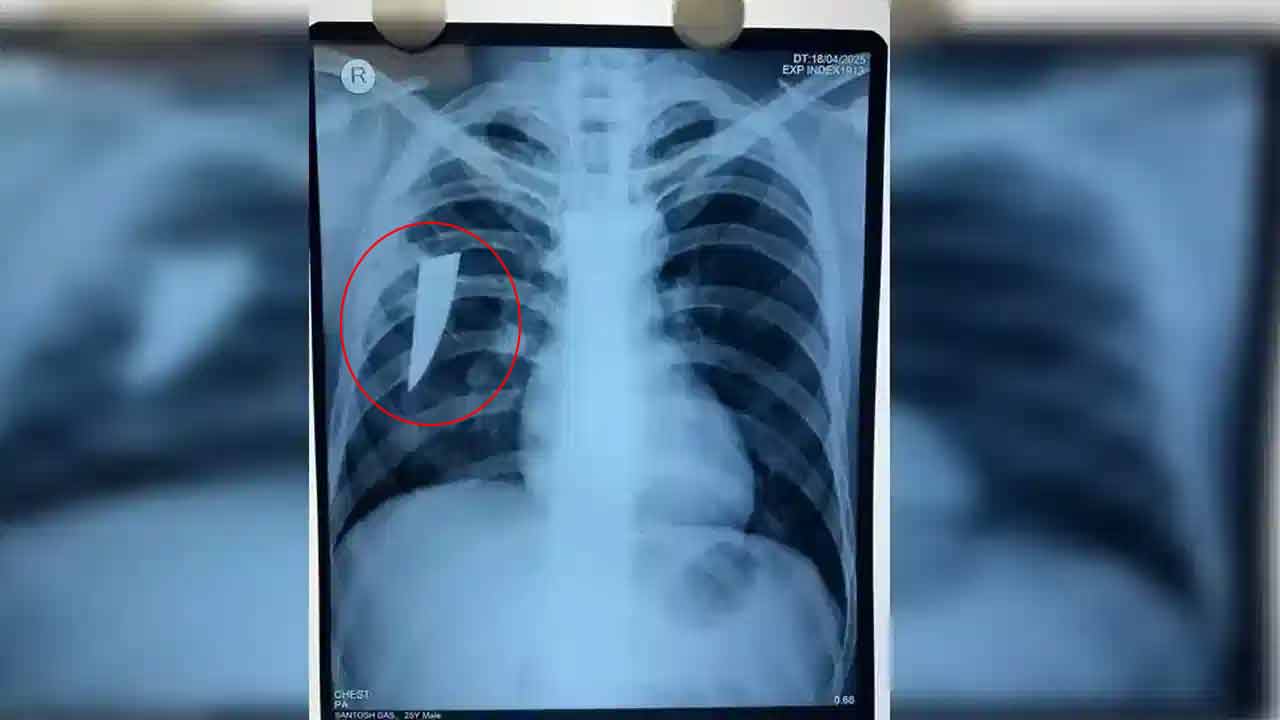

ఒడిశాకు చెందిన ఓ వ్యక్తి మూడేండ్ల క్రితం కూలీ పనుల నిమిత్తం బెంగళూరు వెళ్లాడు. అయితే ఓ వ్యక్తితో ఏర్పడిన గొడవ జరిగింది. దీంతో అతను కూలీ మెడ భాగంలో పదునైన కత్తితో దాడి చేశాడు. ఆ కత్తి ఊపిరితిత్తుల దాకా గుచ్చుకుంది. 8 సెం.మీ. కత్తి మొన భాగం ఊపిరితిత్తుల్లోనే ఉండిపోయింది. శరీరం వెలుపల ఉన్న కత్తి భాగాన్ని మాత్రమే బెంగళూరు వైద్యులు తొలగించారు.

వైద్యులు బాధిత వ్యక్తికి వైద్య పరీక్షలు నిర్వహించారు. సీటీ స్కాన్ తీయగా అతని ఊపిరితిత్తుల్లో కత్తి ఉన్నట్లు గ్రహించారు. దీంతో ఏ మాత్రం ఆలస్యం చేయకుండా సర్జరీ నిర్వహించి కత్తిని తొలగించారు. ప్రస్తుతం రోగి ఆరోగ్యం నిలకడగా ఉందని, ఊపిరి పీల్చుకుంటున్నట్టు వైద్యులు తెలిపారు.